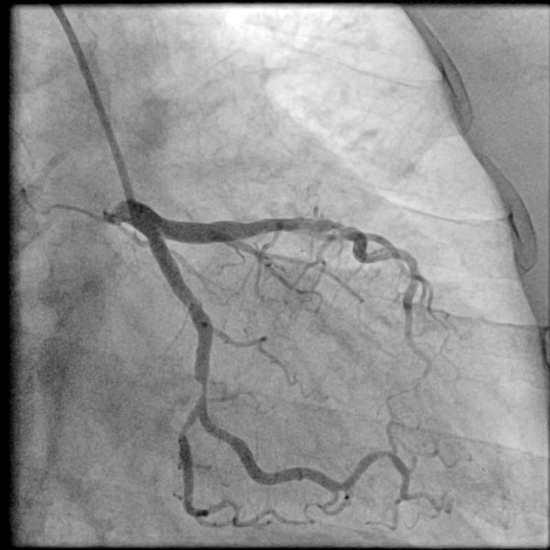

在上面的步骤完成后,我们就有一个鞘管留在手臂上了,这个时候就可以沿着鞘管把造影导管沿着动脉往上送,一直送到心脏冠状动脉开口的地方,注射造影剂就可以让心脏血管显示出来,哪里有狭窄,狭窄有多重?都一清二楚了!这个过程由于血管里没有神经,一般人是没有明显感觉的,当然也不会疼。